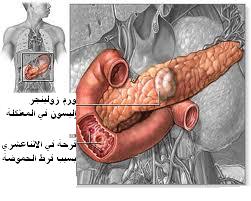

متلازمة زولينگر-إليسون

| Endoscopy image of multiple small ulcers in the distal duodenum in a patient with Zollinger–Ellison syndrome | |

متلازمة زولينجر إليسون Zollinger-Ellison Syndrom هي حالة تسبب إنتاج غير طبيعي في هرمون الغاسترين. يحدث ورم صغير (ورم الخلايا المفرزة للغاسترين) في المعثكلة أو المعي الدقيق يسبب مستويات مرتفعة من الغاسترين في الدم.

تحدث متلازمة زولينجر إليسون بسبب وجود أورام في رأس المعثكلة غالباً والمعي الدقيق العلوي. تنتج هذه الأورام هرمون الغاسترين وتدعى بورم الخلايا المفرزة للغاسترين gastrinoma حيث تسبب المستويات المرتفعة من الغاسترين إنتاج عالي لحمض المعدة.

تظهر الأورام الغاسترينية كأورام مفردة أو متعددة صغيرة. وحوالي نصف إلى ثلثي الأورام المفردة هي أورام سرطانية (خبيثة) تنتشر عادةً إلى الكبد وقرب العقد اللمفاوية.